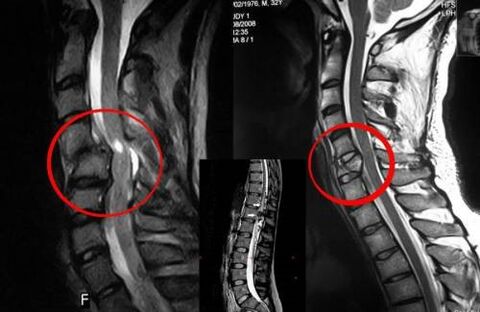

Diagnostika

Lülisamba osteokondroos nõuab õigeaegset konsulteerimist arstiga, kes aitab kahjustatud selja taastada. Kaasaegsed seadmed võimaldavad diagnoosi panna varases arengujärgus. Patoloogia korral pöörduge neuroloogi või ortopeedi poole. Esiteks viiakse läbi vigastatud lülisamba uuring ja kogutakse haiguslugu, seejärel määratakse osteokondroosi tuvastamiseks laboratoorsed ja instrumentaalsed diagnostikameetodid:

- röntgen;

- müelograafia;

- neuroloogiline uuring;

- CT ja MRI;

- tuumamagnetresonants.